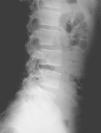

En la visita següent el pacient es presenta amb radiografies que confirmen el diagnòstic d'espondilòlisi L5 unilateral dreta (figs. 1 i 2). D'acord amb el document de consens de la Societat Catalana de Medicina de l'Esport, se sol·licita una gammagrafia òssia planar (GOP) amb tomografia computaritzada per emissió de fotó simple (SPECT). Es decideix continuar amb el mateix tractament i s'assabenta el pacient que serà un tractament a llarg termini.

Figura 2